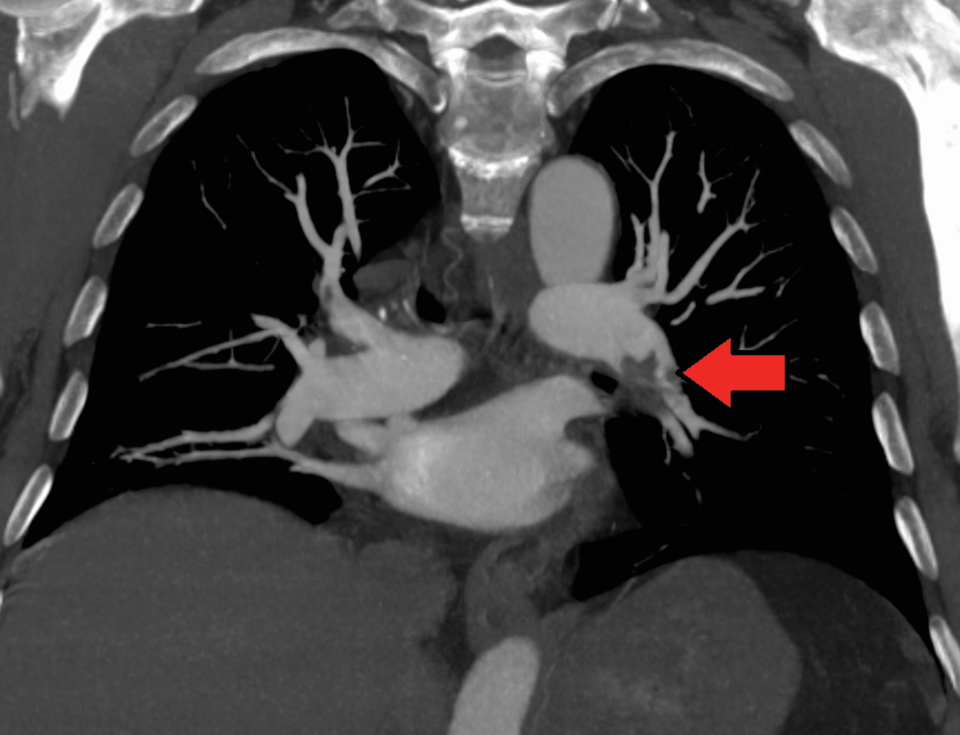

Lungenembolie mit Nachweis eines großen Thrombus innerhalb der rechten Pulmonalarterie. Lungenembolie mit Nachweis eines großen Thrombus innerhalb der rechten Pulmonalarterie. © wikipedia/Bernd Brägelmann Braegel (CC BY-SA 3.0)